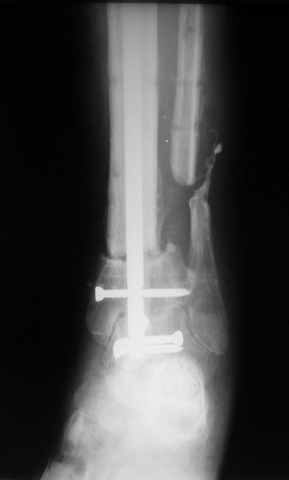

В случае гладкого заживления раны, при условии положительного решения вопроса с металлом, планируем перемонтаж аппарата Илизарова, дополнительную резекцию дистального отломка, выведение полокости голеностопного сустава в правильное положение (см. боковую Р-грамму), одномоментно остеотомия большеберцовой кости. После восстановления длинны голени, по всей видимости, артродез голеностопного сустава.

Рентгенограммы прилагаются. Фото местного статуса выложу в ближайшее время.

Ерсин, мы тоже имеем опыт такой фиксации. Подобную операцию за последние 3 года мы сделали трем пациентам. Снимки одного из них я прилагаю.

К сожалению, ни в одном из этих 3-х случаев мы не получили удовлетворяющего нас результата. Очень трудно провести штифт, введенный антеградно ровно по центру таранной кости. Отсутствие подвижности между диафизом и дистальным отломком большеберцовой кости (после фиксации в аппарате в течение 1-2 мес) очень усложняет проведение штифта в центр блока таранной кости. Поэтому мы от этого пока отказались, и проводим штифт через пятку. При данном варианте фиксации подобных проблем не возникало ни разу.